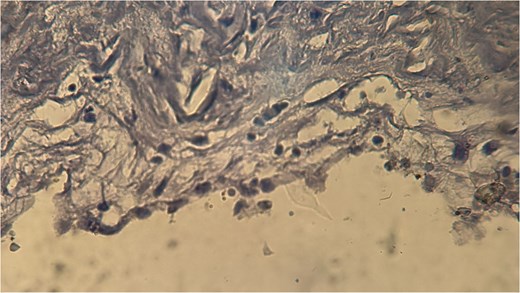

A 60-year-old Moroccan female with no significant medical history presented with chronic periumbilical pain lasting several months, without associated digestive or systemic symptoms, and preserved general condition. Clinical examination revealed periumbilical tenderness. Abdominal ultrasound was unremarkable, prompting an abdominopelvic CT scan, which identified a retroperitoneal inter-aortocaval cystic lesion measuring 86 mm. Surgical exploration revealed a large cystic mass in the mesentery of the small intestine, which was entirely excised. Histopathological examination showed variable-sized cystic cavities with a lymphatic appearance (Fig. 1), lined by flattened and regular endothelium. Some cavities contained pale eosinophilic material interspersed with lymphocytes and areas of red blood cells (Fig. 2). The interstitial tissue exhibited lymphocytic and plasmacytic inflammatory infiltrates. Immunohistochemistry confirmed the lymphatic nature with positivity for Podoplanin/D2–40 (Fig. 3) and CD34 (Fig. 4) and negativity for calretinin (Fig. 5). The patient’s postoperative course was uneventful.

CD34 positivity in endothelial cells, supporting the diagnosis of lymphangioma.